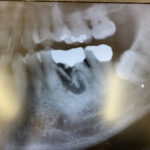

下記の画像をご覧ください。

【患者】 69歳男性

【主訴】 被せ物にモノがよく詰まる 痛みは無い

【既往歴】 高血圧(降圧剤服用中)

左下第1大臼歯の根の半分が割れています。

おまけに黒く写っているところは嚢胞らしきものも。

なんとか奥の根半分で保たれています。

ちなみに白く写っているところは金属の被せ物ものです。

治療法は、麻酔注射後被せ物を外し割れた根の抜歯、

奥の根は使えそうなのでこのままに。

あと暗影部分の掻爬。 止血後抗生剤と消炎剤の投与です。